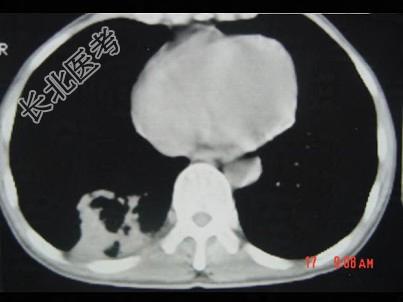

- 单项选择题男,40岁, 胸背疼痛一周,消瘦一月, CT检查如图,最可能的诊断为 ( )

A、右下肺结核

B、右下肺脓肿

C、右下肺炎

D、右下肺肺泡癌

E、右下肺炎性假瘤